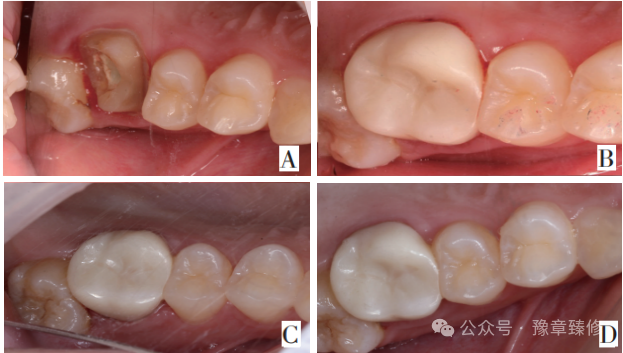

针对髓腔固位深度不足(<3mm)的短冠磨牙,PFRC将修复体向根管内延伸1-2mm,与髓腔固位部分一体成型,使总固位深度达4-5mm,增大粘接面积和机械固位,并优化应力分布(桩分布于颊舌、近远中),有效解决了单纯髓腔固位冠固位不足的问题(图6)[13]。PFRC用于短冠磨牙时,适用于髓腔固位深度不足(<3mm)但需额外根管内固位(延伸1-2mm)的情况。当短冠磨牙根管过度弯曲或根尖未闭合(年轻恒牙)、或根尖周病变未控制(感染风险高),不建议使用PFRC修复。

图6:A-F修复前X线片及临床检查;A:根管治疗术前 X线片;B:根管治疗术后X线片;C:根管治疗术后颊侧近中𬌗龈距离约2mm;D:根管治疗术后颊侧远中𬌗龈距离约2.5mm;E:根管治疗术后舌侧近中𬌗龈距离约2.5mm;F:根管治疗术后舌侧远中𬌗龈距离约3mm。G:𬌗面牙体预备后情况;H:修复体情况;图I-L;2年后复查X线片和口内情况;I:修复后2年复查 X线片;J-L:2年后复查口内情况。